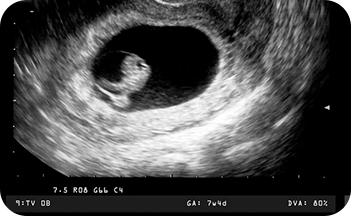

พัฒนาการทารกในครรภ์สัปดาห์ที่ 5-8

“แม่จ๋า หัวใจหนูเต้นแล้ว”

• ขนาดของทารก: ตัวอ่อนในครรภ์จะมีความยาวประมาณ 4 - 25 มิลลิเมตร รูปร่างโค้งงอ

• การตั้งครรภ์ยังไม่สามารถสังเกตเห็นได้ชัด

• ตัวอ่อนเริ่มพัฒนาอวัยวะสำคัญ เช่น หัวใจ ระบบประสาท ตา แขนและขา

• ตรวจพบการเต้นของหัวใจของตัวอ่อนในครรภ์ช่วงอายุครรภ์ตั้งแต่ 6 สัปดาห์ขึ้นไป จากการทำอัลตราซาวนด์ทางช่องคลอดได้ด้วยเครื่องตรวจคลื่นเสียงความถี่สูง